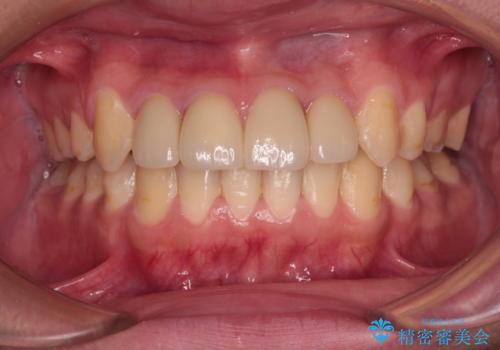

前歯のデコボコとむし歯だらけの歯列 矯正治療と虫歯治療

矯正治療後は上顎前歯4本をオールセラミッククラウンにて補綴治療を行うこととしました。

むし歯が多かったため、ワイヤー矯正中に処置したむし歯が悪化することが懸念されましたが、歯磨きをしっかりと行ってくれたため、とても良好な状態を維持することができました。